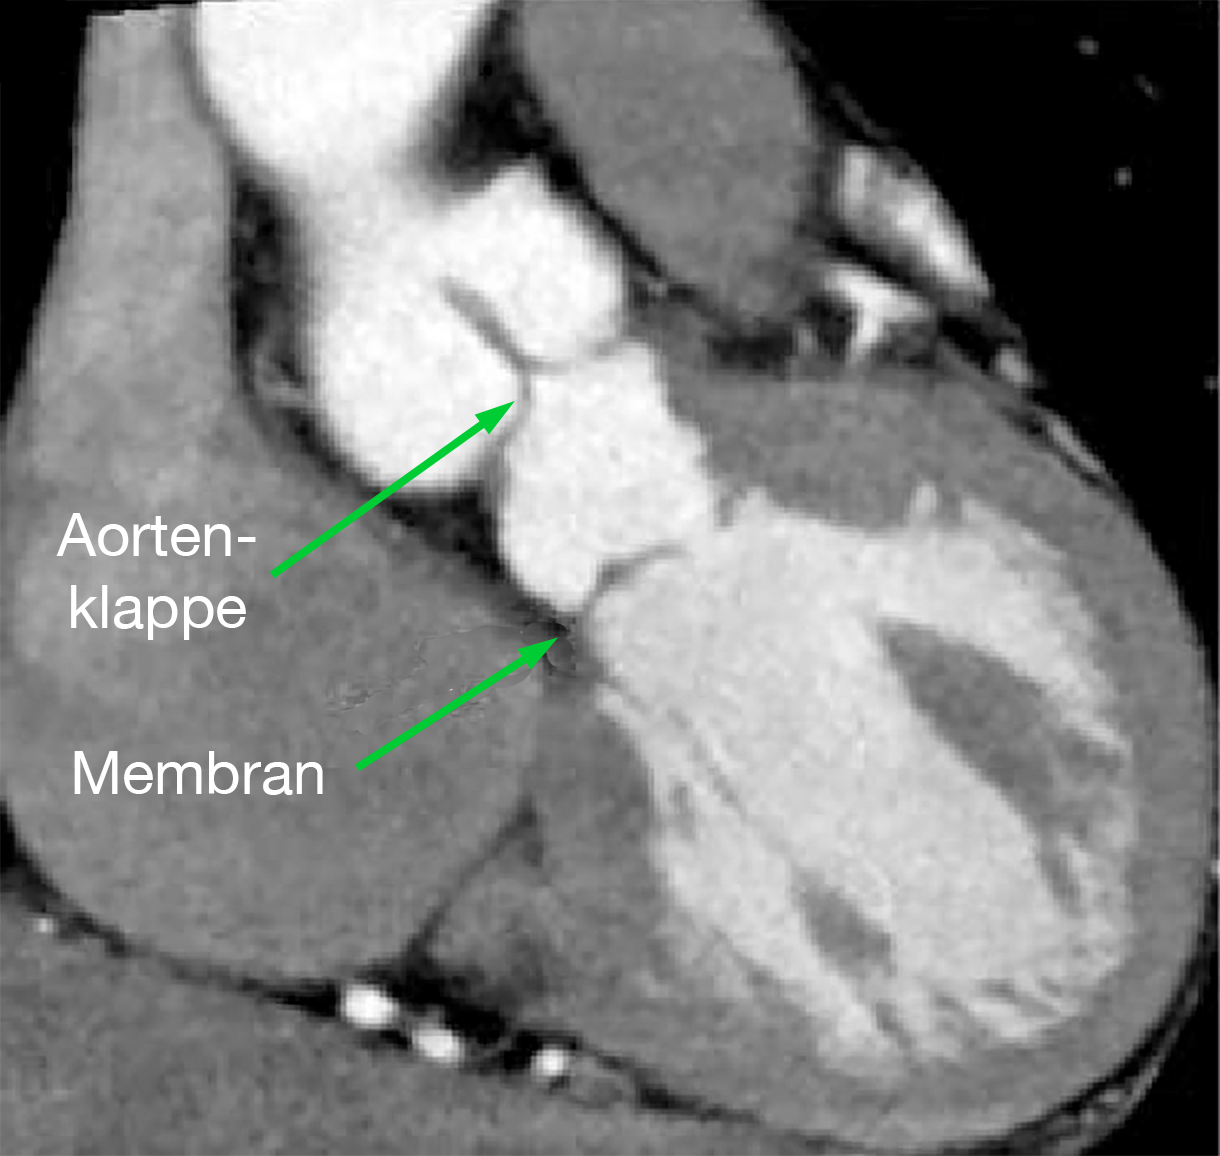

| Supravalvuläre Aortenstenose (Pfeil) im MRT | Membranförmige subvalvuläre Aortenstenose im MRT |

Die MRT-Untersuchung spielt in der Diagnostik eine eigentlich nur untergeordnete Rolle, denn prinzipiell liefert sie dieselben Ergebnisse wie das Echo (Abb. 25 und 26).